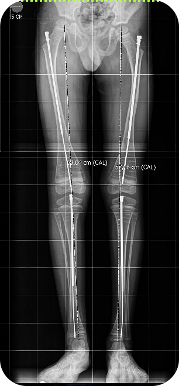

El tratamiento de la Pseudoartrosis Congénita de Tibia y Peroné (PCTyP) ha sido diverso. Todas las técnicas de tratamiento tienen una cuota de complicaciones, pero es la re-fractura y la falta de unión las principales consecuencias que se desean evitar. El objetivo de esta investigación se basa en analizar las técnicas quirúrgicas empleadas en nuestro centro y determinar los resultados. Se realizó un estudio retrospectivo, donde se estudiaron 11 pacientes con esta enfermedad con un seguimiento promedio de 4,73 años (DS±4,56). Todos los pacientes en quienes se utilizó la técnica de Charnley-Williams (CW) lograron la consolidación, la protección del clavo funcionó hasta que el extremo proximal de la tibia queda desprotegido al crecer el hueso y se produjeron angulaciones en esta zona, usualmente en la tibia proximal. Con el uso del clavo endomedular (EM) telescópico de Fassier-Duval (FD) se logra la protección de todo el hueso, inclusive durante el crecimiento. Se concluye que la técnica de CW es un buen método para la resolución de esta enfermedad y con el uso del clavo EM de FD se evita la refractura y se logra la unión permanente a medida que continúa el crecimiento del hueso. La discrepancia de los miembros inferiores es debida a la afectación de la tibia que compromete su crecimiento normal.